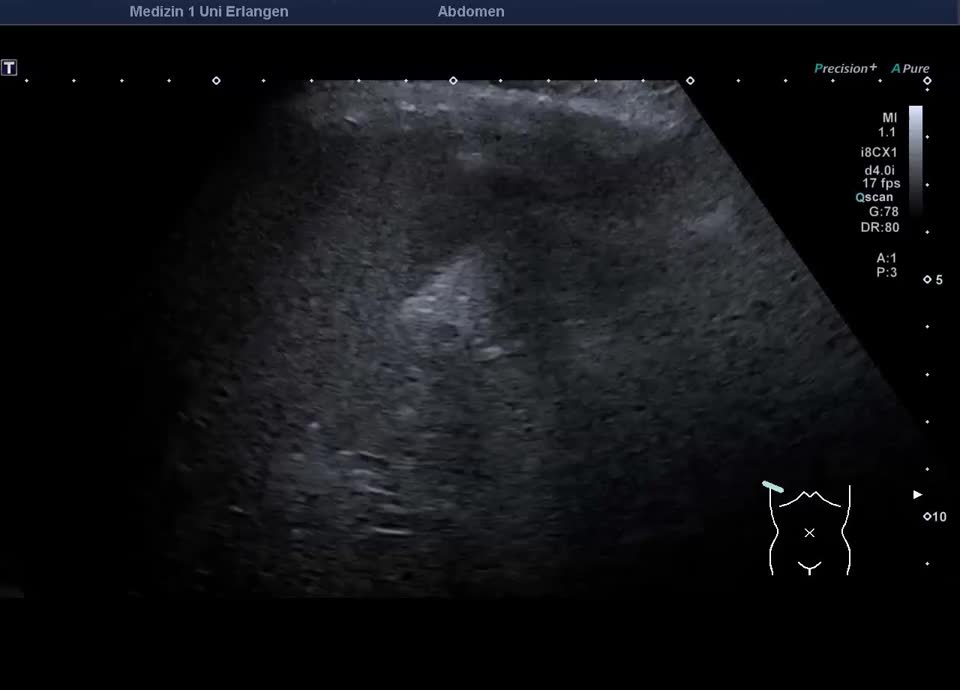

Cholezystolithiasis und Gallenblasensludge